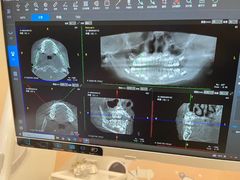

• 德伦口腔(海珠总院)

• -德伦口腔(海珠总院)